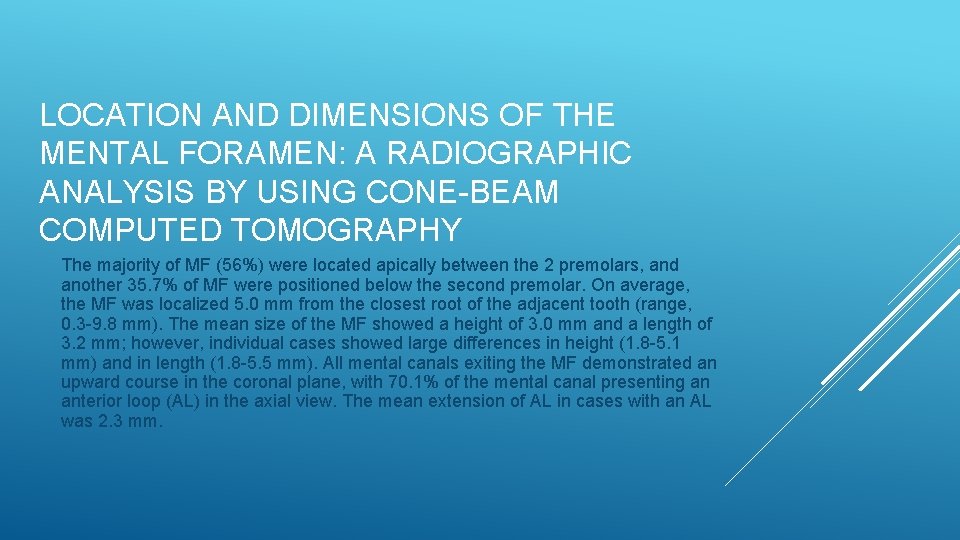

LOCATION AND DIMENSIONS OF THE MENTAL FORAMEN: A RADIOGRAPHIC ANALYSIS BY USING CONE-BEAM COMPUTED TOMOGRAPHY The majority of MF (56%) were located apically between the 2 premolars, and another 35. 7% of MF were positioned below the second premolar. On average, the MF was localized 5. 0 mm from the closest root of the adjacent tooth (range, 0. 3 -9. 8 mm). The mean size of the MF showed a height of 3. 0 mm and a length of 3. 2 mm; however, individual cases showed large differences in height (1. 8 -5. 1 mm) and in length (1. 8 -5. 5 mm). All mental canals exiting the MF demonstrated an upward course in the coronal plane, with 70. 1% of the mental canal presenting an anterior loop (AL) in the axial view. The mean extension of AL in cases with an AL was 2. 3 mm.